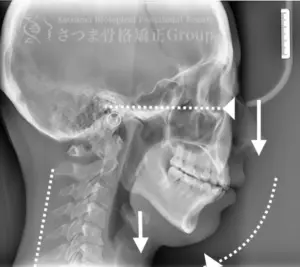

40代男性 F.K様 初回効果

下顎の後方回転あり。 中顔面が伸びて下方に落ちる。 中顔面の奥行きを失っている。 頚椎ストレートネック。 重度の首凝り

Posterior rotation of the mandible The midface is elongated and has dropped downward Loss of depth in the midface Cervical spine straightening (straight neck) Severe neck stiffness

AFTER(マウスピース使用時)

整骨後、形成したマウスピースで形と顎関節の前方回転を誘導。上部頸椎のリリースを促進し、自家矯正力が働きやすいように誘導。蝶形骨口蓋縫合と蝶形骨上顎縫合をモビライゼーションし、可動をブーストし中顔面を短縮。

重度の肩凝りも軽減

After the osteopathy, the custom-formed mouthpiece guides the shape and promotes forward rotation of the temporomandibular joint.

It facilitates the release of the upper cervical spine and encourages the body’s natural self-correcting ability.

Mobilization of the sphenopalatine suture and the sphenomaxillary suture boosts mobility and shortens the midface.